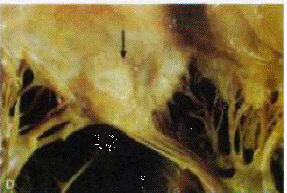

lesioni cardiache sono i corpi di Aschoff. Essi sono formati da aree di

necrosi fibrinoide, circondati da linfociti, macrofagi, occasionali

plasmacellule ed istiociti rigonfi

attivati, chiamati cellule di Anitschkow e di Aschoff.

CELLULE DI ANITSCHKOW E DI ASCHOFF: sono patognomiche per la

malattia. Hanno un citoplasma abbondante amfofilo, nucleo centrale e rotondo,

cromatina disposta a nastro ondulato, da questo il nome di cellule "a forma di bruco"

Le cellule più grandi multinucleate prendono il nome di cellule di Aschoff. Esse si

repertano sia nel pericardio che nell'endocardio. In tal caso si parla di pancardite.